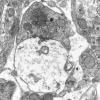

Neuroaxonal dystrophy (3)